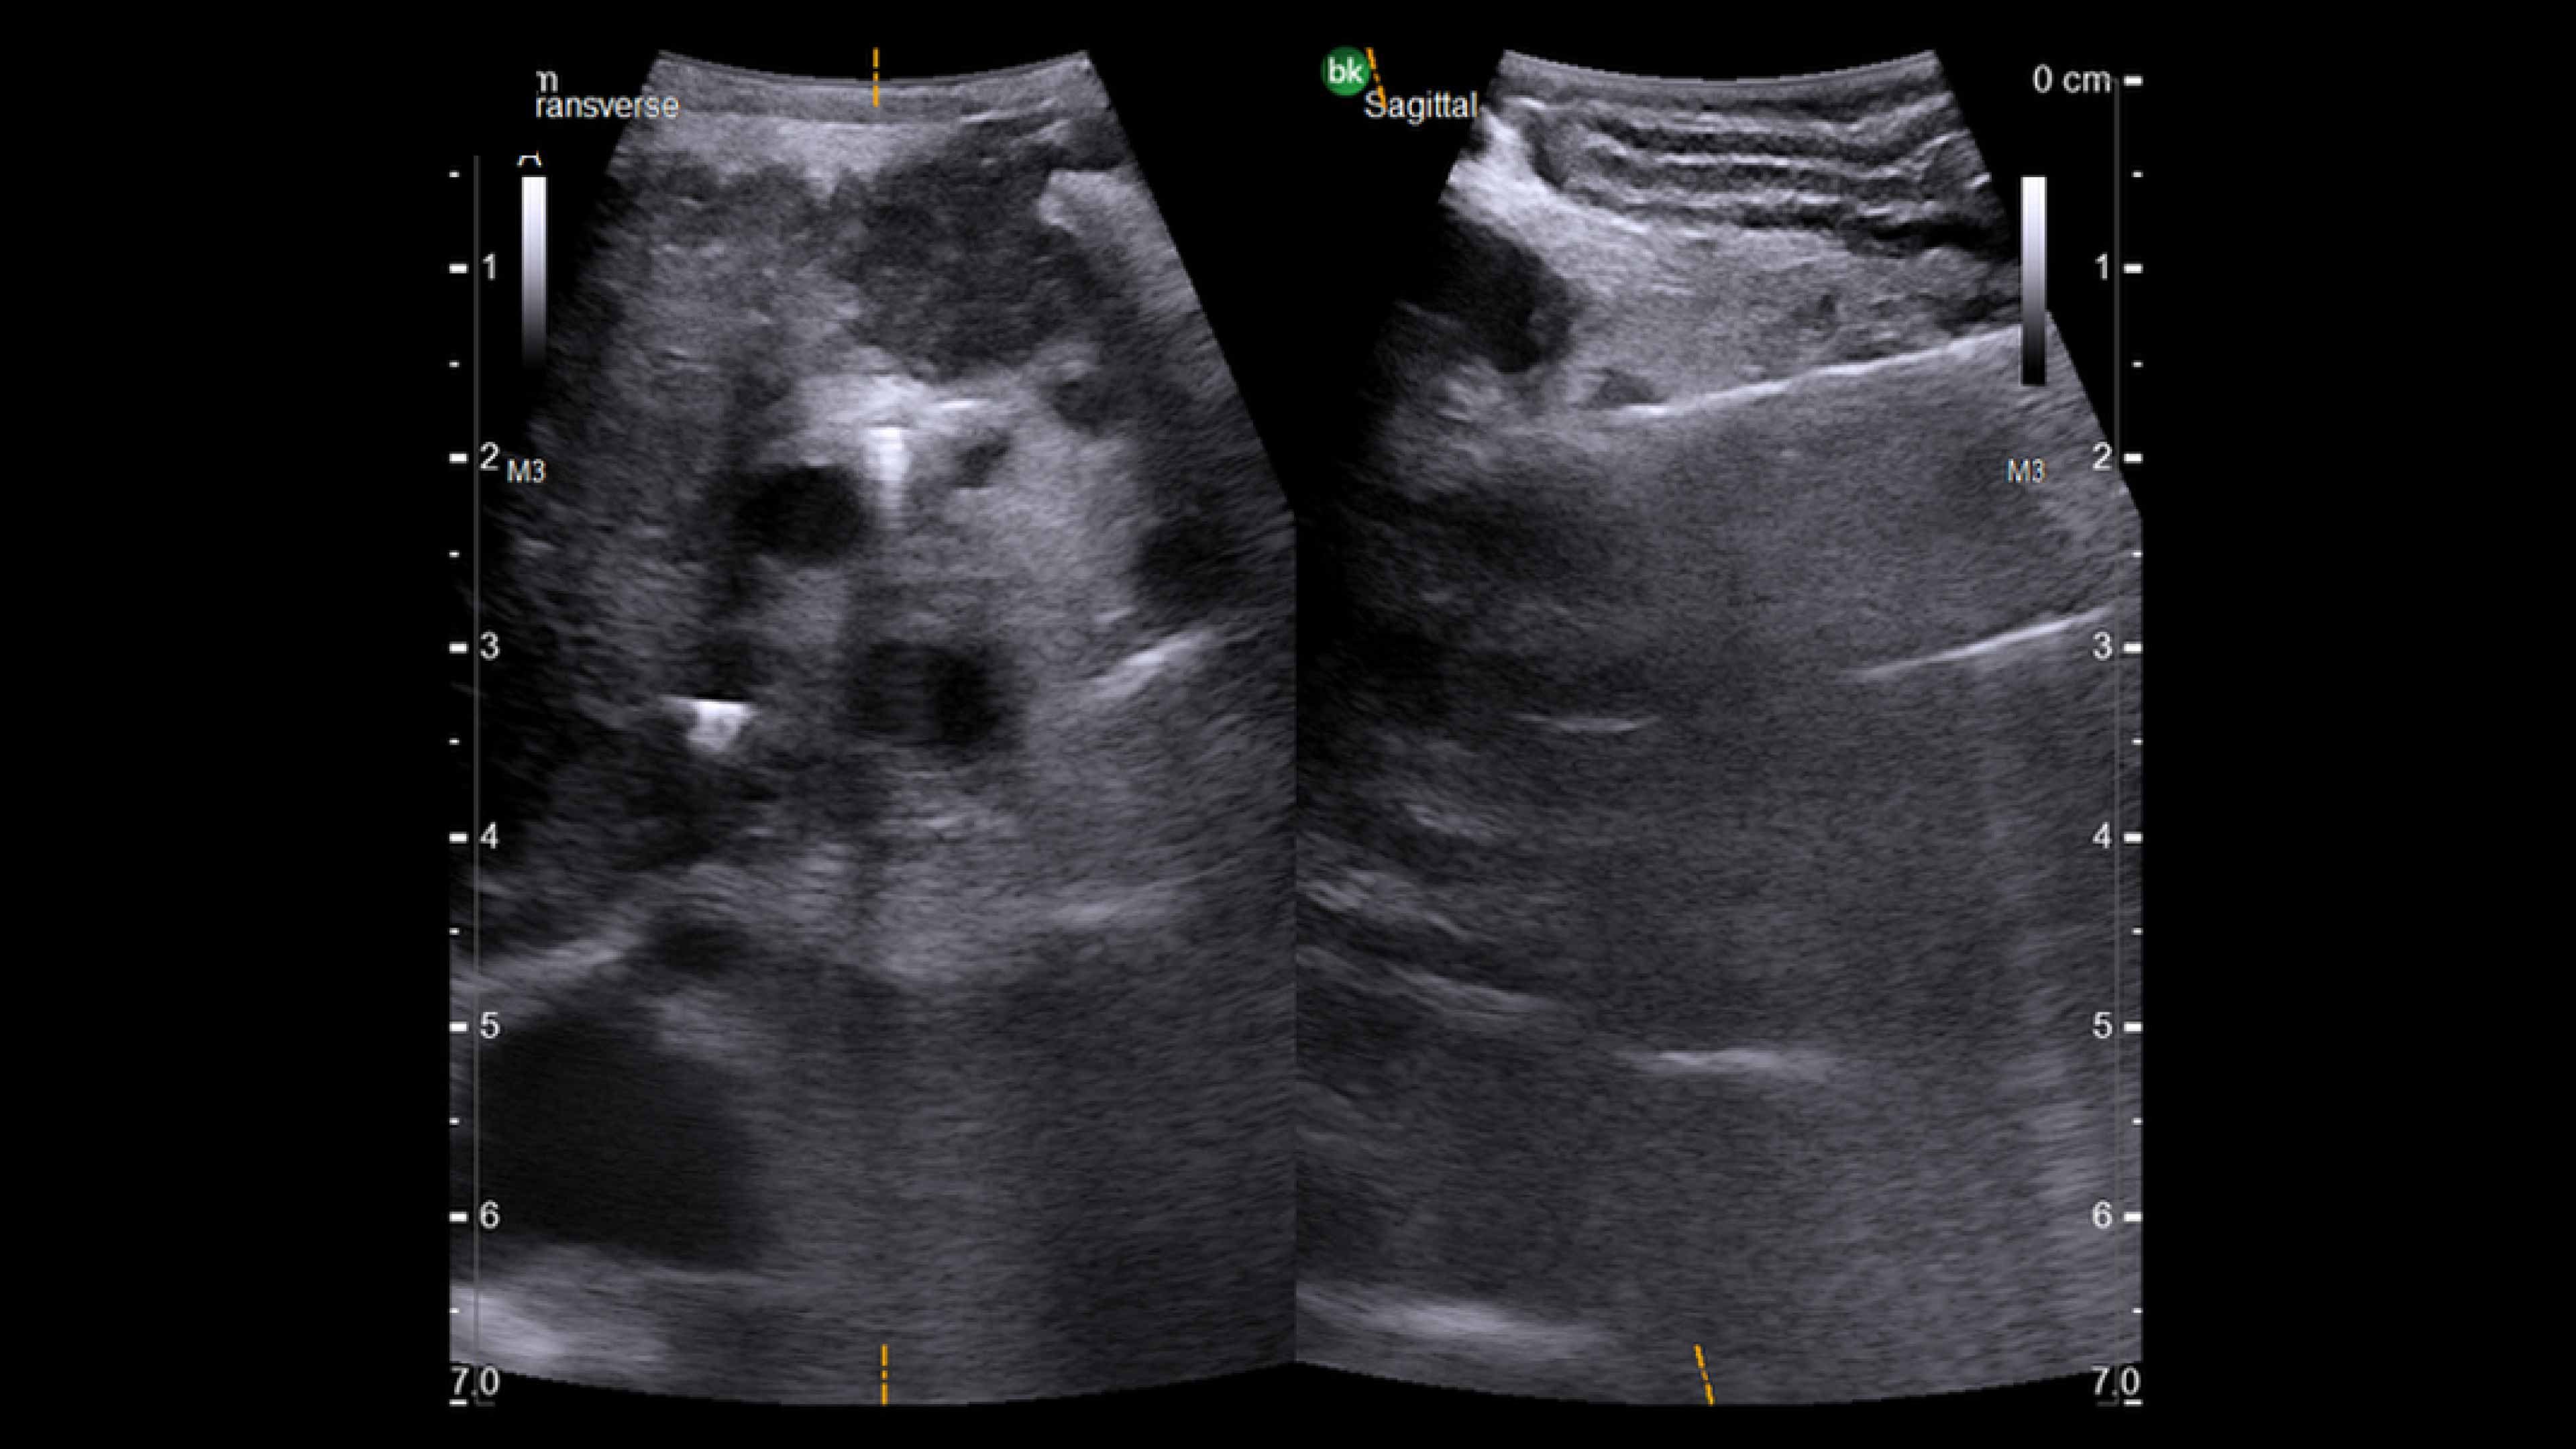

Active imaging supports liver and pancreas tumor resection procedures by helping you visualize complex anatomical variations and relationships to vascular structures, identify tumor location, define adequate margins of resection, and assess surgical planning.

Active imaging with intraoperative ultrasound supports critical decision-making in open or minimally invasive tumor resections.

• Visualize complex anatomical variations.

• Identify tumor location, proximity, and invasion of vasculature.

• Define adequate margins of resection.

• Understand relationship to vascular structures.

• Assess surgical planning and check for vessel patency at the end of the procedure.